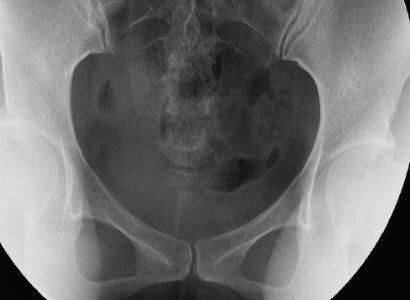

◆造影前先摄盆腔平片一张

◆在透视下缓慢注入造影剂,见子宫和输卵管形态、轮廓能清晰显示,造影剂自输卵管伞端溢出,即拍摄造影片;

造影术影像